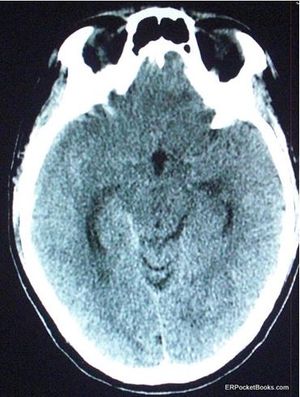

A sudden severe headache with emesis brings a 35-year-old man to the ED. Research on his smart phone has satisfied him that this is a post-coital event and therefore, harmless. He refuses a lumbar puncture.